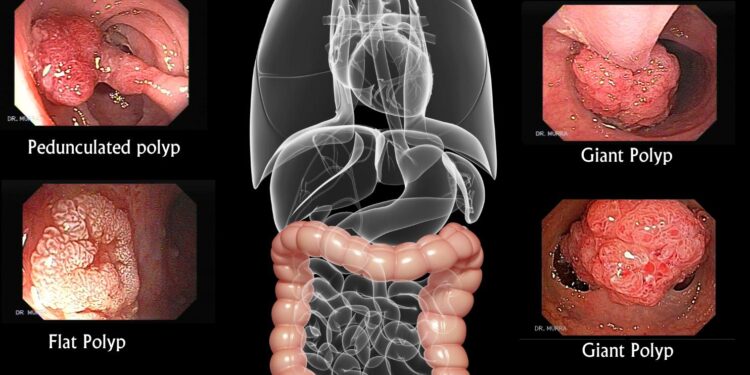

The importance of screenings alongside early detection cannot be overstated when it comes to fighting colon cancer; they significantly enhance the effectiveness of lifestyle modifications aimed at both prevention and treatment efforts. Regular screenings like colonoscopies allow healthcare professionals to detect precancerous growths or early-stage cancers before symptoms manifest themselves. This proactive strategy not only boosts survival rates but also amplifies the benefits derived from lifestyle alterations such as healthier eating habits or increased physical activity levels based on screening results.